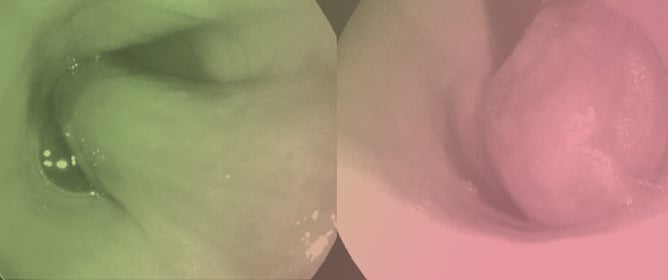

A nine-year-old, 10.5 kg, female-spayed Poodle-mix dog presented with a five-day history of vomiting and regurgitation. Thoracic radiographs revealed an area with increased opacity within the esophageal lumen. A ductal esophageal lesion with intraluminal extension and mild left axillary lymphadenopathy were detected on

A nine-year-old, 10.5 kg, female-spayed Poodle-mix dog presented with a five-day history of vomiting and regurgitation. Thoracic radiographs revealed an area with increased opacity within the esophageal lumen. A ductal esophageal lesion with intraluminal extension and mild left axillary lymphadenopathy were detected on computed tomography. Esophagoscopy revealed a large vascular, obstructive mass with a smooth surface, in the mid part of the esophagus. Endoscopic biopsies were collected, and histopathologic findings were consistent with an inflammatory polyp. Surgical excision of the mass via sternotomy was performed and the mass was sent for histopathologic evaluation. Histopathological examination of the mass revealed an esophageal plasmacytoma with perivascular amyloid deposition, which was confirmed by immunohistochemical staining. There was no evidence of regrowth until 18 months after surgical removal, when evidence of regrowth was identified. The dog had only one episode of vomiting and regurgitation which was resolved after symptomatic treatment.

Figure 1